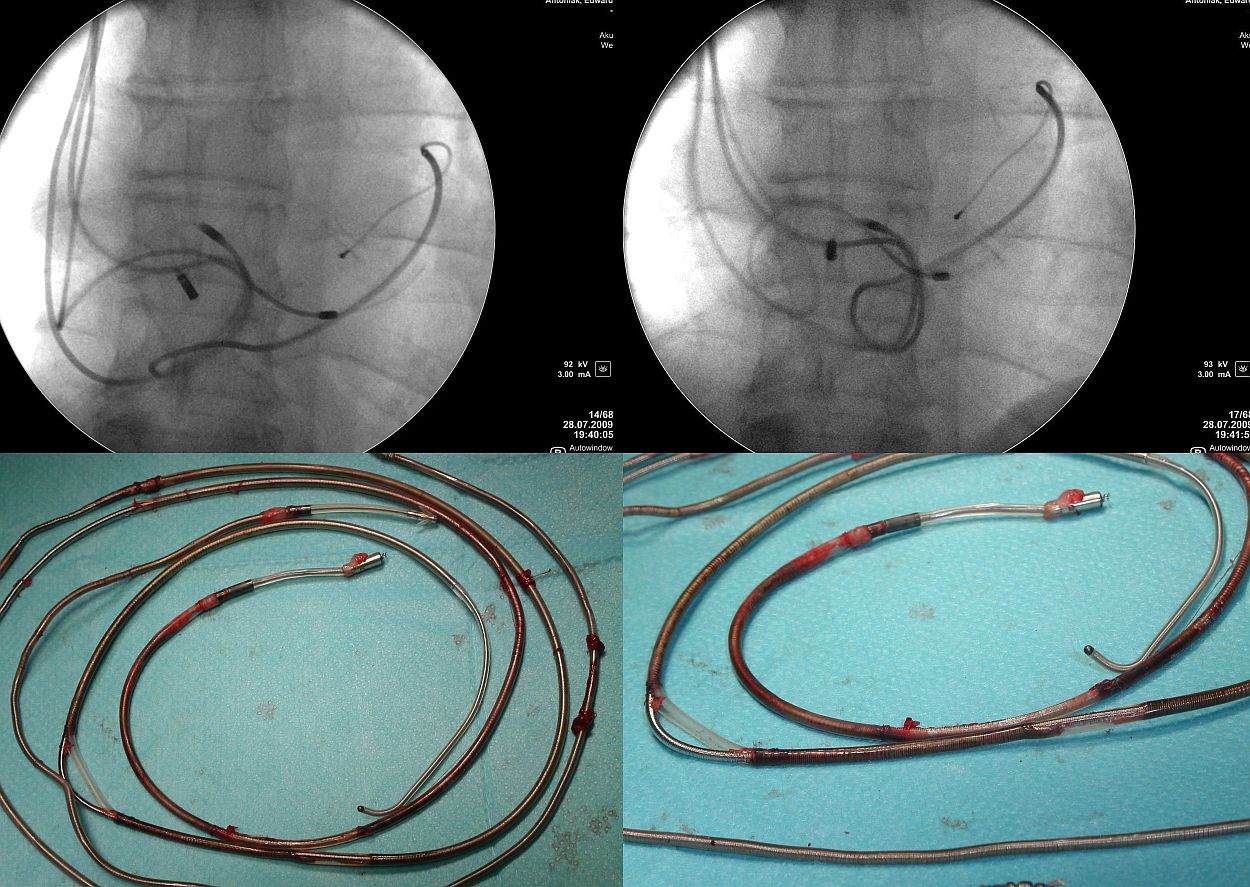

- Okoliczności występowania. Każdy, kto wymienia

stymulatory widział przetarcie elektrody o obudowę

stymulatora. Większość z nas widziała również

przetarcie elektrody o dolny brzeg obojczyka. Tym

zjawiskom można starać się zapobiec poprzez poprawę

techniki zabiegu implantacji. Identyczne pod względem

morfologicznym przetarcia występują w układzie żylnym,

a przede wszystkim w obrębie prawego serca. Niezależnymi

czynnikami zwiększającymi prawdopodobieństwo wystąpienia

przetarcia są: wiek i liczba elektrod w układzie

sercowo-naczyniowym, obecność w układzie elektrody

wchodzącej do zatoki wieńcowej oraz obecność zbędnych

nieprawidłowych pętli w prawym przedsionku bądź prawej

komorze. Czyli czas i wzajemny kontakt poruszających się

w różnych kierunkach elektrod mają znaczenie decydujące.